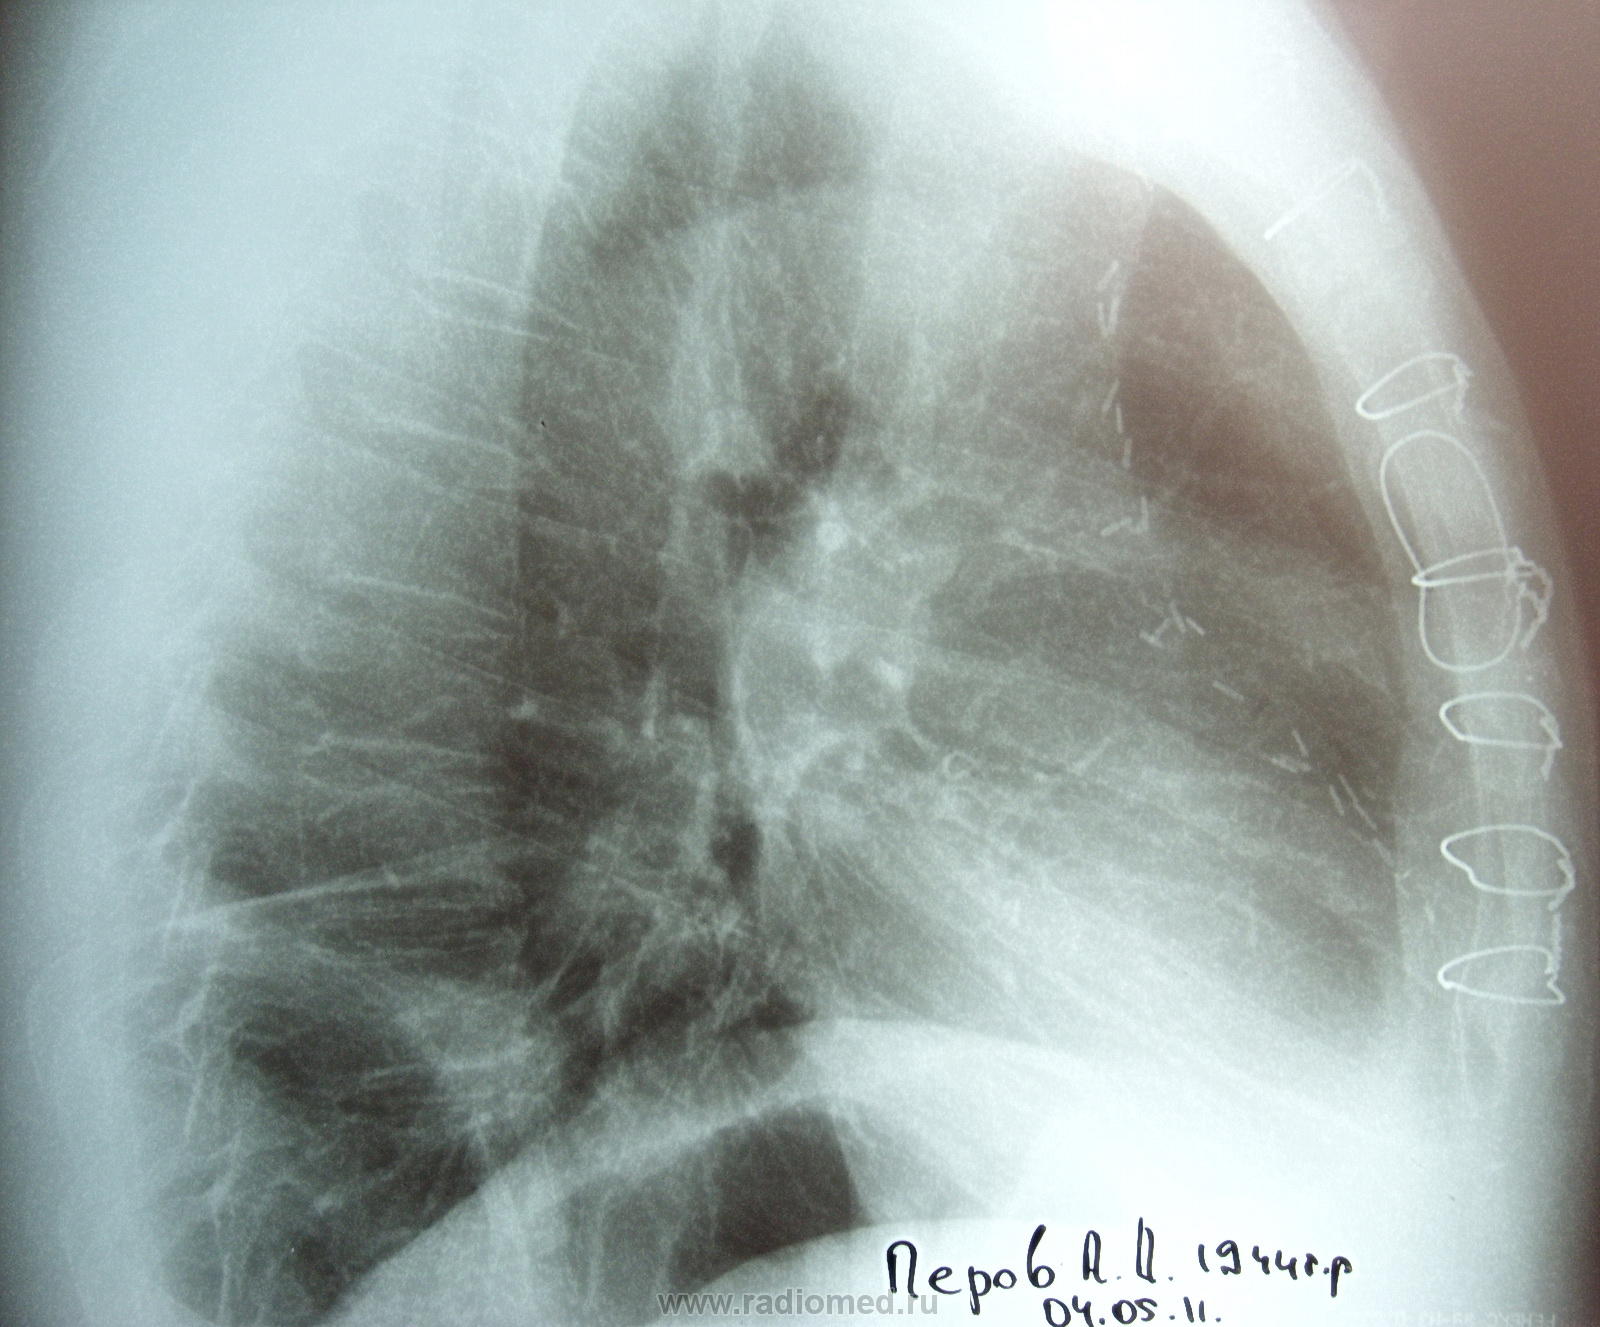

Справа в н отделе (проекция S 9) - инфильтрация ? На боковом какая-то подозрительно ровная треугольная тень рисуется в этих отделах (шварта?)

С учетом операции... я бы в первую очередь подумала об инфаркной пневмонии с затянувшимся течением. Сегментарная, S9 справа. И рекомендовала бы контроль после противовоспалительного лечения. При отсутствии динамики - линейная или компьютерная томография. И, разумеется, поднять архив.

лёгком определяется дисковидный ателектаз. У меня возник вопрос по поводу ретростернального пространства, в боковой проекции,  есть ли там воздух? Мне показалось что есть.

Справа я вижу два фокуса воспалительных в н/д, фиброз в с/д.

Острого не вижу.Эмфизема, участки пневмосклероза(не исключаются перенесенные инфарктные пневмонии).Двусторонний деформирующий бронхит.